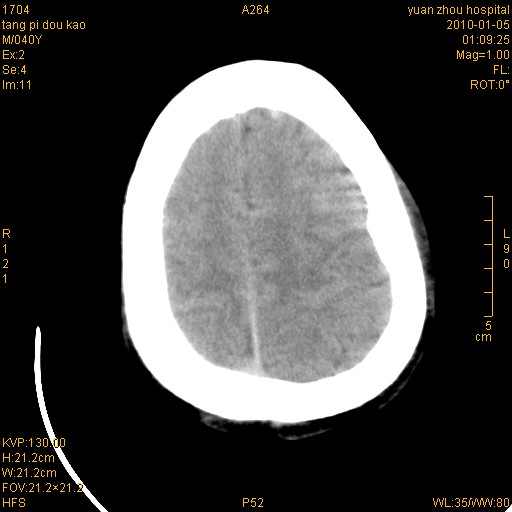

标题: CT23986:M 40Y 外伤数小时

1)左侧颞枕部硬膜外血肿。2)右侧额部硬膜下血肿。3)双侧额叶及右侧基底节下部脑挫裂伤。4)蛛网膜下腔出血。5)脑水肿。6)左侧前组筛窦及左侧额窦炎症。

挫裂伤,颅内血肿,蛛网膜下腔出血,脑肿胀。